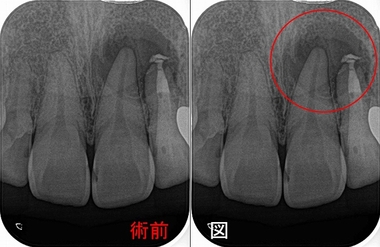

レントゲン

かなり大きな根尖病変が見られます。

根尖病変は左上1にもかかっていますが、電気歯髄診査では左上1は生活反応があり神経は問題無いと考えました。

側切歯は予後の悪い歯になるので、もし歯を保存したければ早目に歯内療法専門医に相談した方がいいと思います。